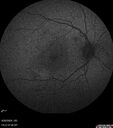

Severe NPDR

53 year old man with blurred vision (needs glasses).

Diabetic for 10 years with poor control

VA 20/32 OU